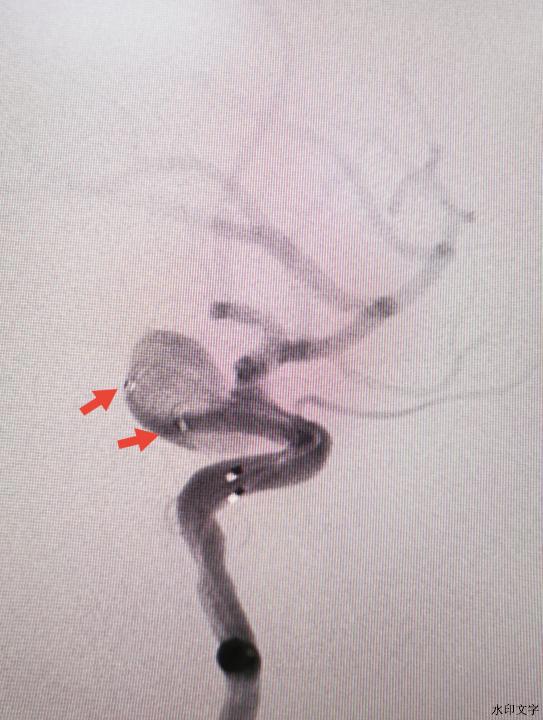

近日,家住大丰区新丰镇季某某,女,59岁,既往有“高血压、糖尿病”史3年多,一直自行服药治疗,清晨8点多在家时突发剧烈头痛,随后意识模糊不清,被家人发现后报120紧急送到我院急诊室行头颅CT检查示:蛛网膜下腔出血。随即启动卒中绿色通道,神经外科副主任医师沈华第一时间到达急诊室,仔细查看病人并分析病情:自发性蛛网膜下腔出血80%左右考虑颅内动脉瘤破裂导致,这种疾病病情凶险、死亡致残率极高,如果发生再次破裂出血死亡率高达70%左右,需要立即行头颅CTA血管检查明确诊断才能制定下一步治疗方案,很快头颅CTA结果显示:左侧颈内动脉后交通段巨大动脉瘤,大小约12.4*7.6mm。理论上脑动脉瘤越大越容易再次破裂,病情危急人命关天,卒中中心诊疗组会诊后决定急诊行血管内弹簧圈栓塞动脉瘤微创治疗方案,得到家属同意后神经介入团队、导管室医技护师、麻醉医师相继被紧急召集进行术前准备工作,导管室无影灯下气氛凝固、手术紧张有序,经过二个多小时的血管内弹簧圈栓塞动脉瘤手术终于顺利完成。术中采用双微导管交替栓塞技术从而避免了急性出血期植入支架的再出血风险,目前患者经过精心治疗已痊愈出院。该例患者的成功救治表明了我院神经介入在治疗复杂性颅内动脉瘤技术方面有了新的突破。

术前颈动脉后交通段巨大动脉瘤(12.4*7.6mm)

术中双微导管技术 术后动脉瘤完全栓塞